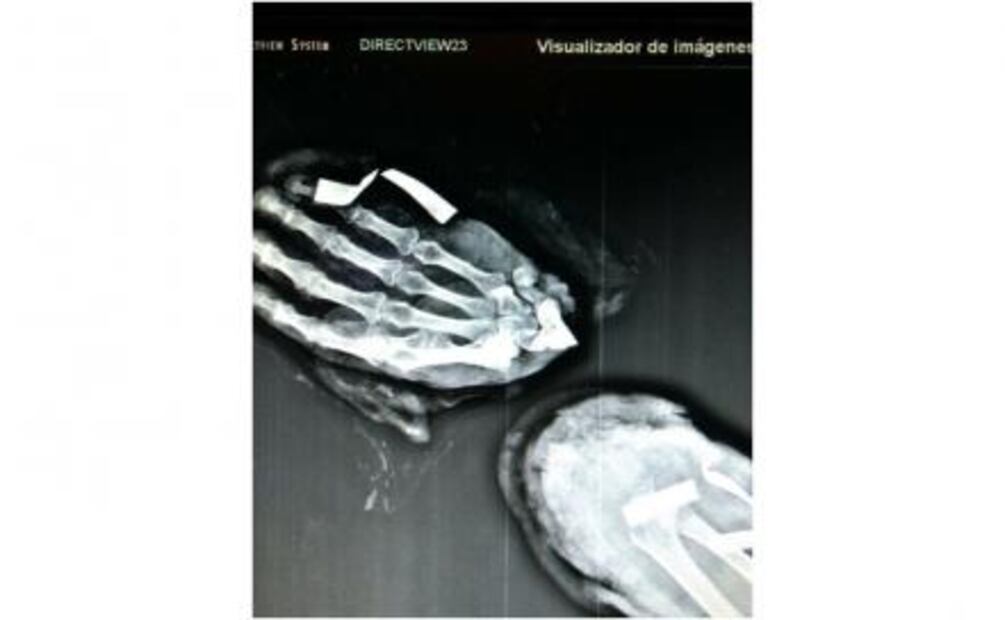

“El caso de este paciente es una carpectomia de la primera fila del carpo y se hace una fusión con el resto del radio; se centraliza la mano para una forma anatómica y se fija con un apartado ortopédico, que es un fijador externo. Se usaron clavillos de fijación y probablemente sea suficiente para que haga una artrodesis, que es una fusión de la muñeca”, indicó.

Y agregó: “La complejidad es que es un procedimiento de microcirugía y de reconstrucción de una extremidad, entonces hay que ir poco a poco; localizar los vasos sanguíneos primero, perneabilizarlos y hacerle la anastomosis, que médicamente es el término que usamos para conectar los vasos sanguíneos. El término medico es un reimplante de mano que se hace con una técnica de microcirugía”.